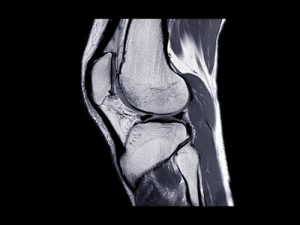

Os compartimos un artículo publicado en la Revista Española de Artroscopia y Cirugía Articular. Se titula: Resultados clínicos de la técnica anteromedial versus la técnica transtibial en la reconstrucción del